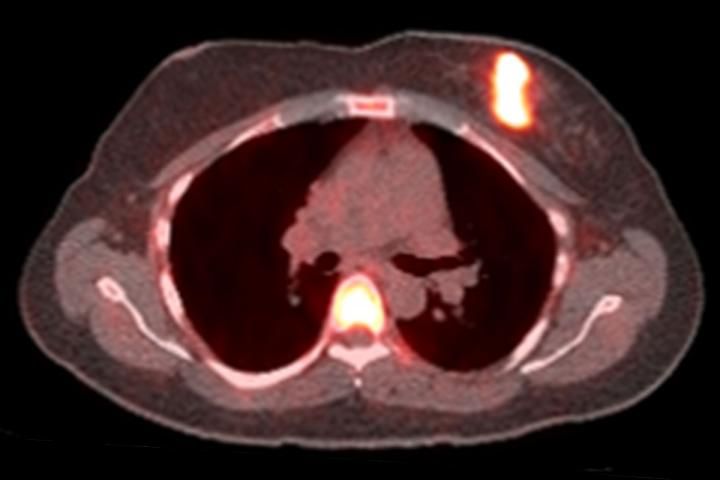

Pet Ct Scan Of A Patient With Breast Cancer A Trace Amount Of Download Scientific Diagram

Breast Positron Emission Tomography PET scan is an imaging test that uses a tracer radioactive substance to look for symptoms of breast cancer. PETCT positron emission tomography is a widely utilized nuclear medicine imaging modality in which fluorodeoxyglucose FDG follows glucose uptake into highly metabolic tissues most commonly used in the evaluation of staging treatment response or recurrence of various cancers. A PET scan is often combined with a CT scan known as a PETCT scan.

Proper management requires accurate diagnosis and evaluation of spread of tumor and the PETCT scanner provides sophisticated imaging to assess the original tumor as well as metastatic disease. How the Test is Performed A PET scan requires a small amount of radioactive material tracer.

A positron emission tomography PET scan shows images of organs and tissues and how they are functioning. FDG breast cancer PET staging therapy response Positron-emission tomography PET has proven useful in the evaluation of many cancers. In a way the use of PET scanning would be for a certain in-between situation when something unusual shows up on a screening mammogram but there is not yet a confirmation of breast cancer.